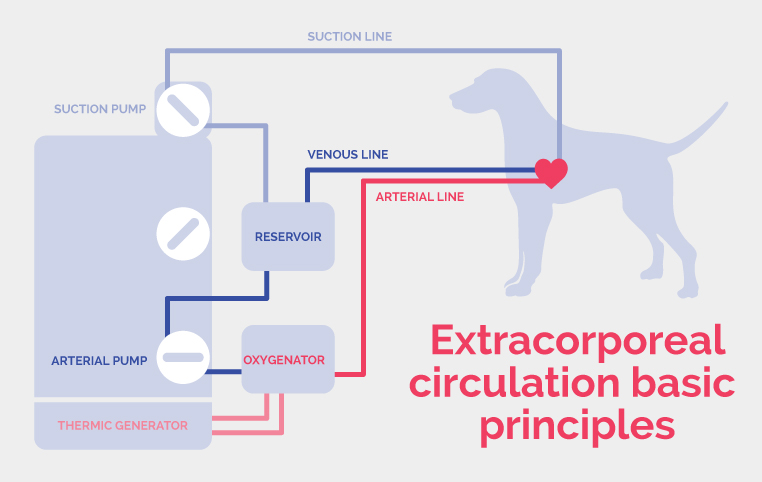

Heart-lung bypass machine – centerpiece of the intervention

The technical and human platform are important, the team must have a perfect cohesion but the most crucial point is the heart-lung bypass machinery which represents quite a challenge in small individuals.

At HOPia, we are able to operate on Chihuahuas as small as 1,4 kg.

In small breed dogs, extracorporeal circulation is a technical challenge because of their very small total blood volume. The tubing is customized to small individuals such as miniature dogs and cats. Heart-lung bypass procedures induce cardiac arrest, thus enabling the surgeon to repair the valves on a motion-free heart. The bypass takes over the lung and heart (pump) functions during the intra-cardiac surgical time.

What are the diffrent parts of the heart-lung bypass machine?

-

a venous line

-

two suction lines, one for the thoracic cavity and the other for the heart cavity

-

a tank

-

an oxygenator

-

a thermic generator able to control the blood and thus the body temperature

-

two suction pumps

-

an arterial line

-

an intermediate line for arterial blood sampling

-

a monitor displaying all the parameters’ live values

-

an anaesthesia circuit for isoflurane and sevoflurane

- an hemofilter

- a monitor displaying all the parameters’ blood values

The perfusionist, working hand-in-hand with the surgeon and the anaesthetist, must master the extracorporeal circulation technique for the procedure to be a success.

Doctors Sabine and Jean-Hugues Bozon are the ones giving instructions to the perfusionist.